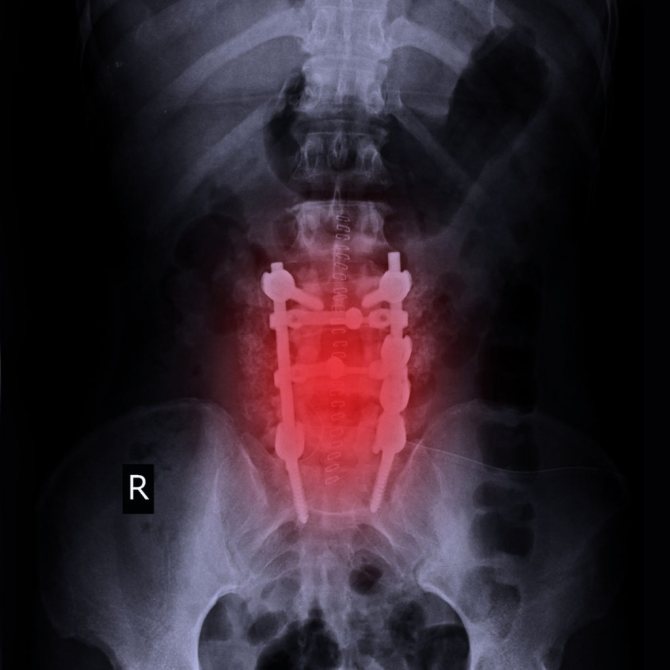

Дискэктомия поясничного отдела позвоночника может быть частью более крупной операции, которая включает в себя:

- Ламинэктомию (операция по устранению компрессии спинного мозга путем удаления части кости для расширения позвоночного канала)

- Ламинотомия – рассечение одной или нескольких дуг позвонков.

- Фораминотомию (удаление части диска или костной шпоры (остеофита), которые ущемляют нерв, поскольку выходят за пределы позвонка)

- спондилодез (хирургическая операция по соединению двух или более позвонков с целью устранения избыточной подвижности позвоночного столба).

Техника операции заключается в рассечении кожных покровов длиной до 10 см, мышцы отводятся в стороны, а затем производится иссечение грыжевого выпячивания, возможно — дужки позвонка (ламинэктомия) в случае необходимости. По показаниям проводят пластику диска искусственным материалом или собственной костной тканью из подвздошной кости. После удаления измененных тканей хирург останавливает кровотечение и ушивает ткани в обратном порядке.

Дискэктомия шейного отдела проводится при грыжах, цервикалгиях, компрессии нервных корешков и сосудов с нарушением кровотока в голове и других изменениях со стороны дисков. Она требует общей анестезии, доступ — чаще передний, то есть пациента укладывают на спину, а разрез проводят в передней части шеи. Сквозь разрез хирург достигает позвонков, удаляет измененную ткань или весь диск целиком, а на его место устанавливает синтетический имплант или собственную ткань пациента, изъятую из подвздошной кости.

Чтобы обеспечить правильное заживление, позвонки в зоне удаленного диска фиксируются металлическими пластинами — спондилодез. Рана ушивается в обратном порядке, перевязываются или коагулируются кровоточащие сосуды.